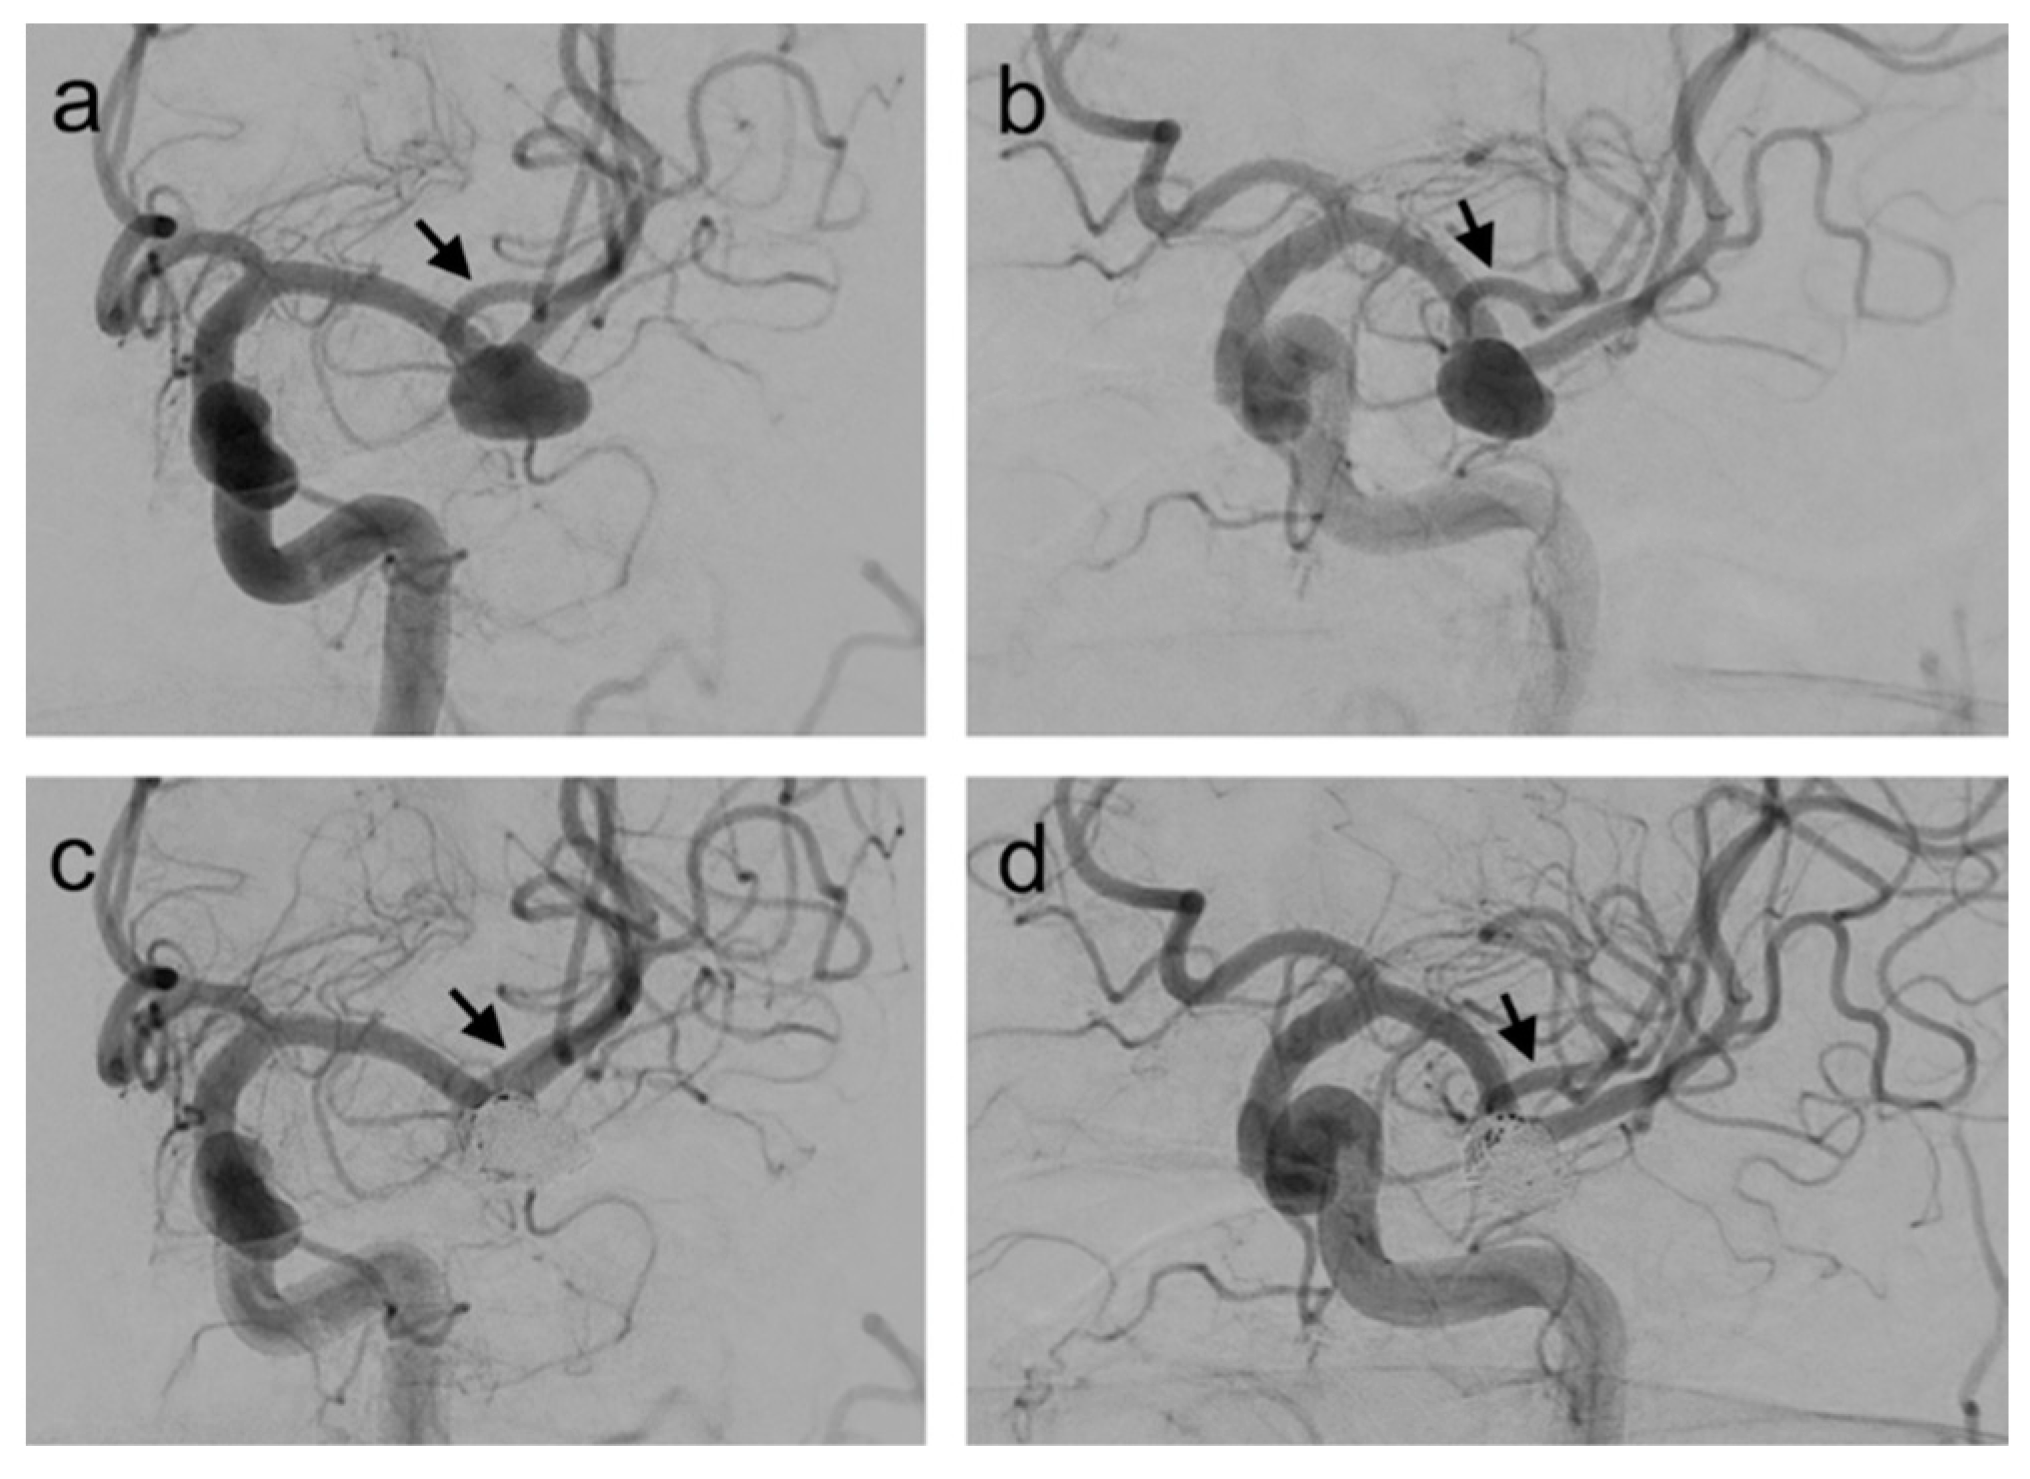

- Park, K.Y.; Kim, B.M.; Kim, D.J.; Chung, J.; Lee, J.W. Y-configuration stenting for coiling of wide-neck bifurcation aneurysms using Low-profile Visualized Intraluminal Support Junior. J. Neurointerv. Surg. 2019, 11, 400–404. [Google Scholar] [CrossRef] [PubMed]